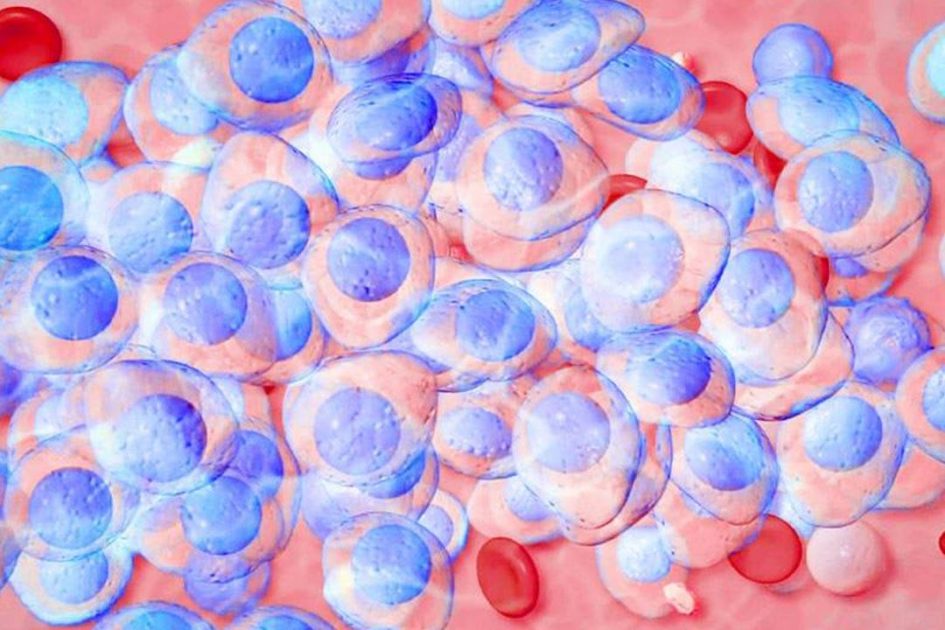

وهناك العديد من الدراسات التي أجمع فيها العلماء بأن مرض tuberculose يكون ناجما عن الإصابة بجرثومة تدعى المتفطرة السلية والتي تهاجم الرئتين في أغلب الأحيان.

كما ذكرنا، فإن الإصابة بمرض tuberculose يكون عن طريق جرثومة والتي بدورها تهاجم الرئئتين أي الجهاز التنفسي للإنسان المصاب واذي بدوره من الممكن أن ينتقل عبر الهواء.

وينتقل مرض tuberculose عبر الهواء حيث أن المصابون يبصقون ويسعلون وكذلك يعطسون بالهواء الأمر الذي يساعد على نشر الجراثيم في الهواء وما يكون سوى استنشاق الهواء من قبل الشخص السليم حتى يصاب بالعدوى.

وعلى غير المعتاد، كانت قد خرجت منظمة الصحة العالمية لتشير إلى أن 1/3 سكان العالم يحملون سل مخفي أي ربما أنهم كانوا قد أصيبوا بجرثومة السل ولكنه غير ظاهر عليهم أعراض هذا المرض وكذلك فإنهم لا ينقلونه.